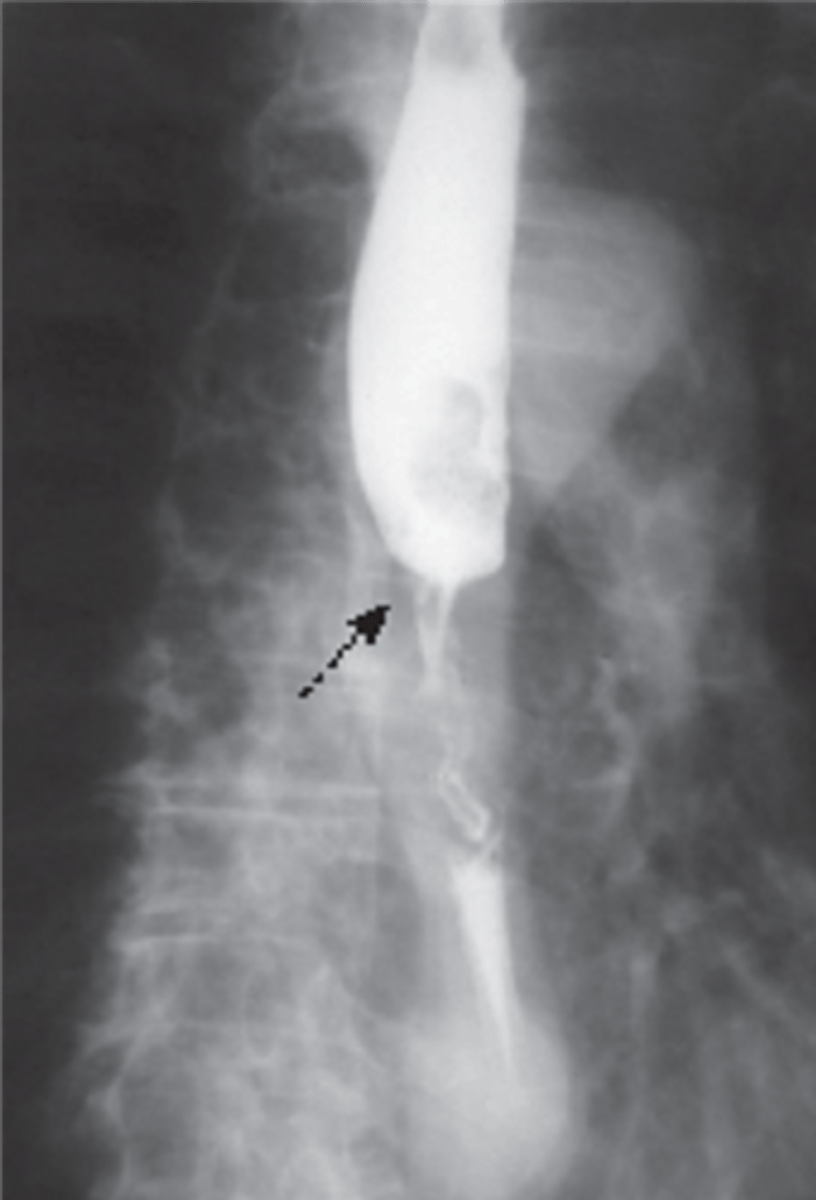

corkscrew esophagus- sign of diffuse esophageal spasm